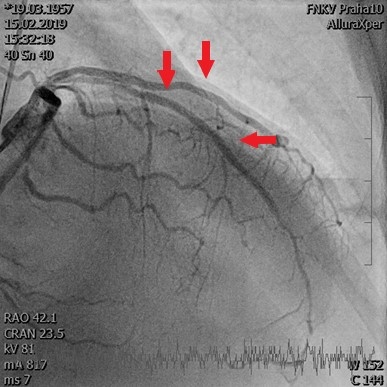

Obr. 1 – Příjmové EKG – elevace úseku ST na přední stěně, blokáda pravého Tawarova raménka staršího data a fibrilace síníByla provedena urgentní selektivní koronarografie s nálezem nemoci tří tepen – ramus interventricularis anterior (RIA) 95 % a 80 %, ramus intermedius (RIM) 90 %, ramus marginalis sinister I 80 %, ramus marginalis sinister II 80–90 %, arteria coronaria dextra 70 %. Léze na RIA byly ihned ošetřeny primární PCI s implantací dvou lékových stentů, dále byl implantován jeden lékový stent do RIM (obr. 2A, 2B). Echokardiografie prokázala středně těžkou systolickou dysfunkci levé komory srdeční s akinezí v povodí RIA, stopovou mitrální regurgitaci. Laboratorně zjišťujeme vysoce senzitivní troponin T s maximem 3 820 ng/l. Druhý den hospitalizace byl pacient extubován, nadále byl spontánně ventilující, oběhově stabilní.

Obr. 2 – (A) Koronarografický nález na levé věnčité tepně, šipkami označeny dvě významné stenózy na RIA a významná

stenóza na RIM. (B) Koronarografický nález po primární PCI culprit léze na RIA, dále ošetřena také významná stenóza

na RIM, šipkami označeny místa implantovaných stentů. PCI – perkutánní koronární intervence; RIA – ramus interventricularis

anterior; RIM – ramus intermedius.